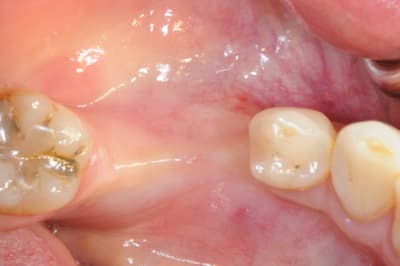

CAS 1

demande de restauration avec implant, mais, ne veut pas entendre parler de greffes et greffons.

la ROG lui semble plus "naturel".

1-2-3 situation de départ